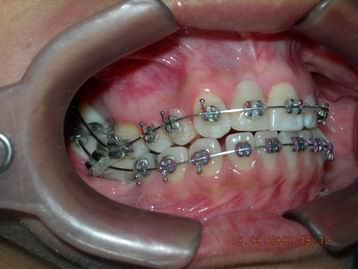

FASE INICIAL DO TRATAMENTO ORTODÕNTICO (vista lateral esquerda) |

FASE INICIAL DO TRATAMENTO ORTODÕNTICO (vista lateral direita) ANTES DA ABERTURA DO ESPAÇO PARA O INCISIVO LATERAL DIREITO